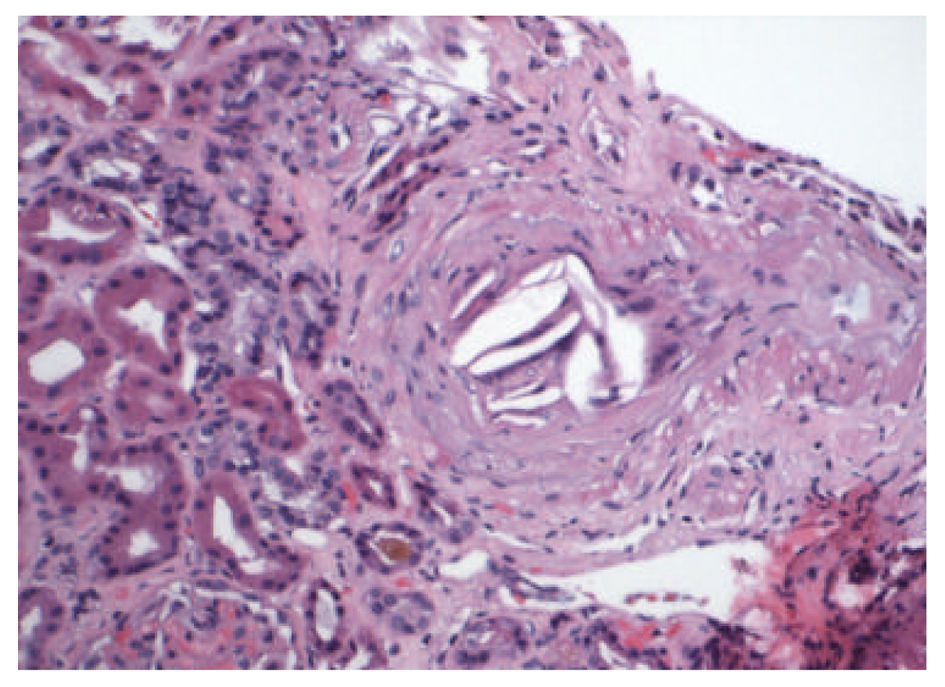

Renal ultrasound showed normal size kidneys with bilateral cortical thinning, and no hydronephrosis. CT scan of the abdomen and pelvis showed a 3.2 cm infrarenal abdominal aortic aneurysm with mural thrombus of undetermined age. Patient was started on dialysis and a percutaneous renal biopsy was performed. The biopsy specimen revealed that 8 out of 26 glomeruli were globally sclerotic and the remaining glomeruli showed diffuse mesangial matrix expansion and focal patchy interstitial fibrosis (Fig. 1). The medium sized arteries were focally occluded by cholesterol clefts surrounded by granulomatous inflammation, and small arterioles with severe arteriolonephrosclerosis, without evidence of vasculitis (Fig. 2, 3). The patient was discharged home with outpatient dialysis arrangements, and he has remained dialysis dependent.

![]() Click for large image | Figure 2. Medium sized artery with focal occlusion by cholesterol clefts, surrounded by granulomatous inflammation (Hematoxylin & Eosin, × 2,000). |